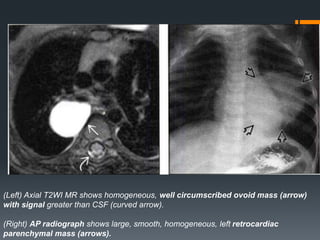

(Left) Axial T2WI MR shows homogeneous, well circumscribed ovoid mass (arrow)

with signal greater than CSF (curved arrow).

(Right) AP radiograph shows large, smooth, homogeneous, left retrocardiac

parenchymal mass (arrows).

BRONCHOGENIC CYST They aredevelopmental lesions that result from abnormal ventral budding of the tracheobronchial tree between the 26th and 40th days of gestation. • Location Mediastinal location is more common than pulmonary o Mediastinal 65-90% Majority in the middle mediastinum Typically para tracheal, carinal, or hilar Pericarinal most common o Pulmonary: Majority in the medial third of the lungs, More frequent in the lower lobes Typically do not communicate with airway and do not contain air, Air presence indicates infection. CT Findings • NECT o Homogeneous well circumscribed lesion o Cyst contents variable: Water to proteinaceous o Hence CT attenuation is variable

• CECT o Well-defined,typically with nonenhancing or minimally enhancing thin wall o More prominent wall enhancement and wall thickening may be seen with infection o No central enhancement MR Findings • TlWI : o Well-circumscribed lesion o Homogeneous signal intensity unless infected o Variable signal due to varying amounts of proteinaceous material, but usually water signal o Imperceptible wall • T2WI: Signal is almost always equal to or greater than cerebrospinal fluid (CSF) • STIR: Markedly increased signal, equal to or greater than CSF • Tl C+ : o May have a thin rim of mild enhancement o Thicker enhancing wall implies infection o No central enhancement

(Left) Axial T2WIMR shows homogeneous, well circumscribed ovoid mass (arrow) with signal greater than CSF (curved arrow). (Right) AP radiograph shows large, smooth, homogeneous, left retrocardiac parenchymal mass (arrows).